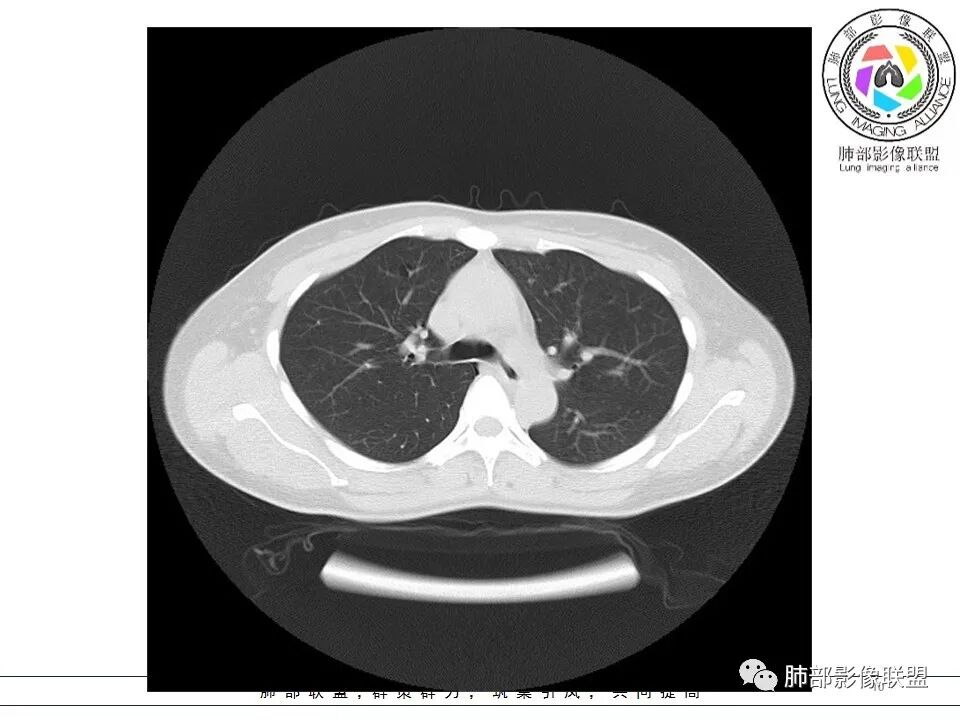

女,38岁,无症状,胸片体检发现两肺可疑病灶。

?其母亲有肺大泡,2017年手术。影像学特点:两肺胸膜下多发的大小不等囊状气腔,壁很薄或无可见的囊壁,小囊的边界比较清楚,大囊的形态比较怪异,以两下肺为著。考虑肺组织细胞增生症,鉴别肺淋巴管肌瘤病。

小叶中心,胸膜下囊,比较大,规则:

无其他伴随征象

BHD主要影像表现特征:    1、两肺内肺囊肿:80%以上的BHD患者会出现肺内囊肿,且倾向于基底部近胸膜下分布,特别是纵膈侧肺膜下,囊肿形状不规则、囊肿可大可小,肺内囊肿多毗邻肺下动脉或静脉近端,胸部CT上囊肿分布和特点对诊断有提示意义。    2、继发自发性气胸:BHD患者发生气胸风险是正常人的5倍,BHD患者的气胸发生率约为 1/4,气胸复发率则高达59%。   3、肾肿瘤:(常为双侧性、倾向于嫌色细胞组织学亚型)   4、皮肤表现(为面、颈部纤维性毛囊瘤、毛盘瘤)